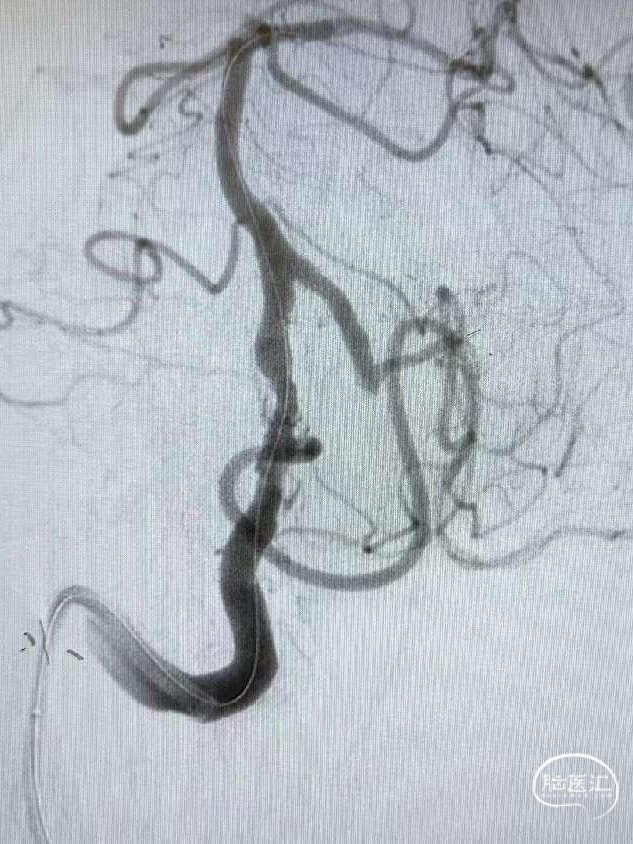

球扩后造影观察。

赛诺NOVA®颅内药物洗脱支架 2.75*12mm输送至病变段。

10atm压力释放赛诺NOVA®颅内药物洗脱支架。

术后造影:RV4段狭窄较前明显改善。